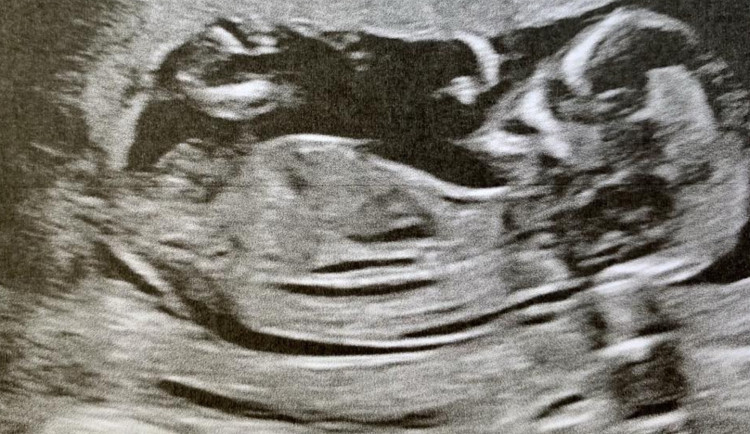

Tým vědců z Lékařské fakulty Masarykovy univerzity v Brně studoval mechanismy prvního embryonálního dělení, které představuje klíčový vývojový moment lidského zárodku. Podle výzkumníků prostorové uspořádání buněčného dělení, které nastává krátce po oplození, významně ovlivňuje šanci na úspěšný vývoj. Jejich výsledky opravují schémata z embryologických učebnic založená na datech z myší. Aktuální výzkum publikoval vědecký časopis Nature Communications.

Při prvním embryonálním dělení se mateřské a otcovské chromozomy poprvé potkávají. „Nová kombinace genetické informace musí být rovnoměrně distribuována do dvou dceřiných buněk. Jejich dalším dělením pak vzniká celý nový organismus. Zjistili jsme, že prostorová orientace buněčného dělení oplozeného vajíčka není náhodná a významně ovlivňuje šanci na úspěšný embryonální vývoj," uvedl autor studie Volodymyr Porokh z ústavu histologie a embryologie univerzity.

Pochopení těchto mechanismů má zlepšit efektivitu asistované reprodukce a kvalitu péče o páry, které mají potíže s početím. Odborníci uvádějí, že jen zhruba z každého třetího počatého lidského embrya se narodí miminko. O tom, proč je vývoj tak neúspěšný, mají dosud jen omezené informace, protože použití lidských zárodků pro výzkum je přísně regulováno. Brněnský tým využil časosběrné záznamy vývoje embryí pořízené při léčbě neplodnosti ve spolupracujícím centru asistované reprodukce.